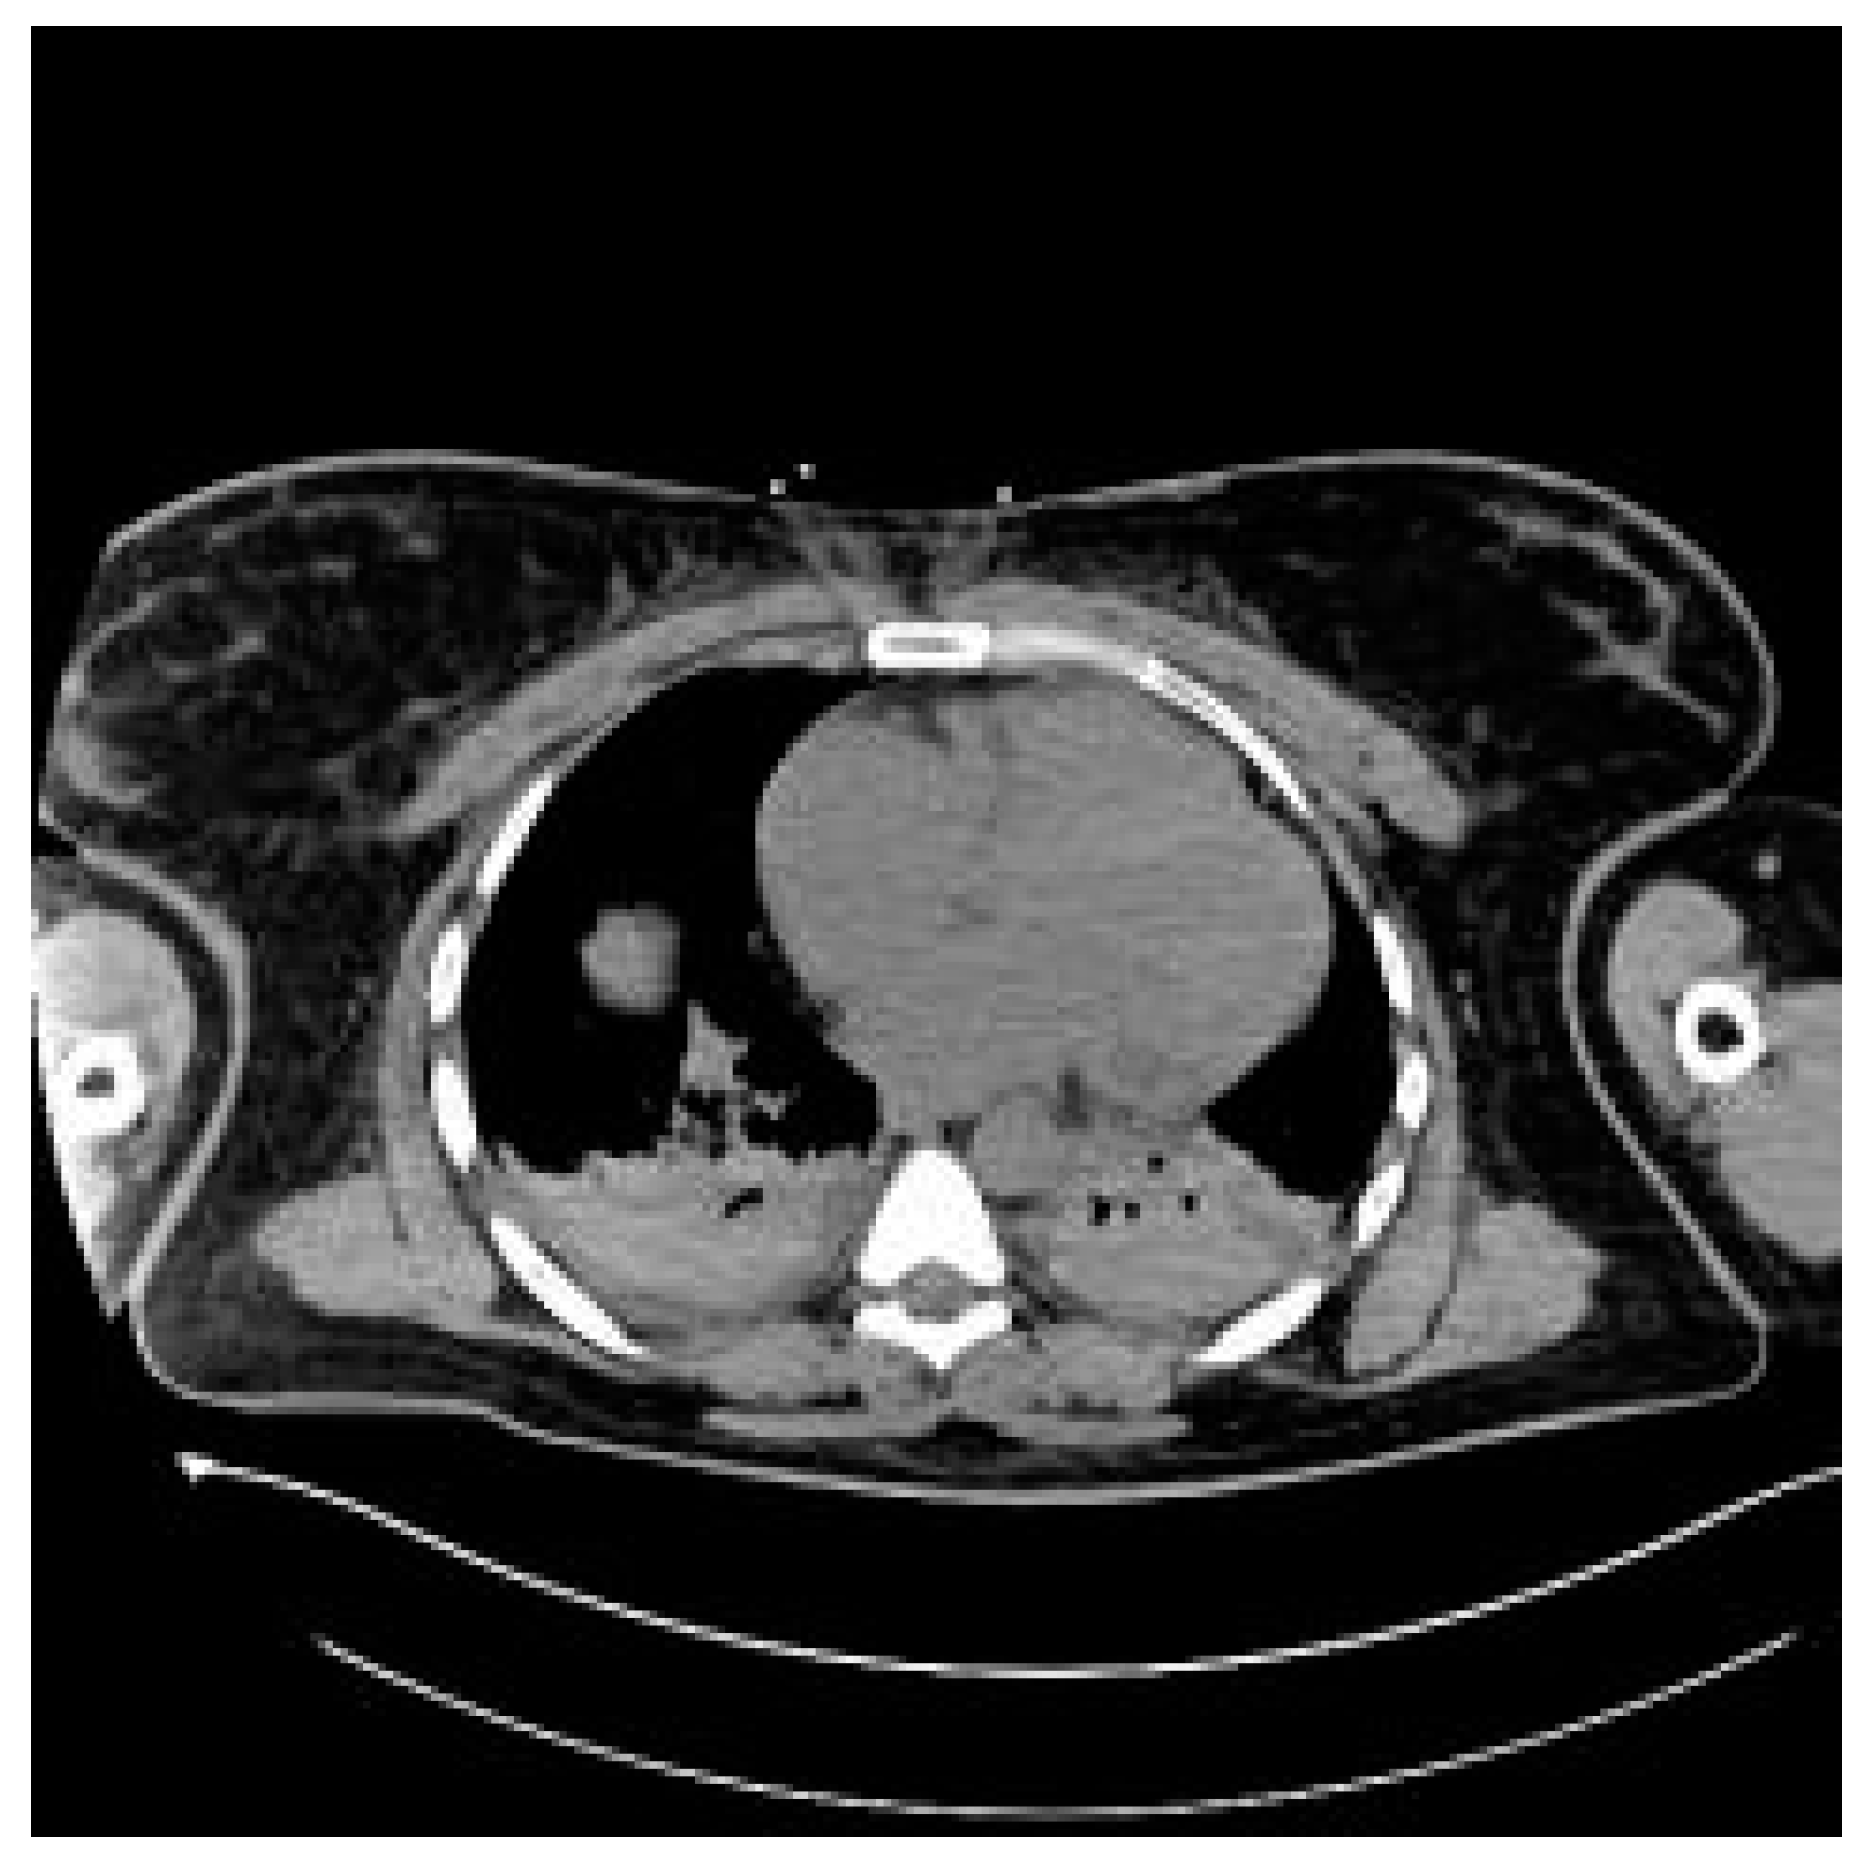

The patient was transferred to the postoperative intensive care unit (ICU) in a serious general condition. A control CT of the brain confirmed cerebral edema, areas of hypodensity and SAH (Figure 2). An angio-chest CT revealed a small amount of fluid in both pleural cavities, up to 12 mm. Areas of parenchymal consolidation were visible bilaterally in the dorsal parts of the lungs, partially with an air bronchogram, which may correspond to atelectatic inflammatory changes. No signs of pulmonary embolism were found. An echocardiogram was performed, which showed good global left ventricle contractility, an estimated eviction fraction of 50%, and no signs of cardiopulmonary overload; as well, it found significant symmetrical hypertrophy of the cardia (14 mm) and traces of aortic insufficiency. An abdominal CT revealed an enlarged liver and a small amount of free fluid in the pelvis (Figure 3). Following the scans, the patient was transferred to an obstetrics operation theater, where an immediate cesarean section was performed due to high risk of maternal mortality, delivering an extremely immature, low-weight fetus. Regardless of the highest level of neontological care, fetal resuscitation procedures were abandoned, palliative care was provided and fetal death was confirmed within 2 h.

Figure 3. Chest CT with lung consolidations bilaterally.